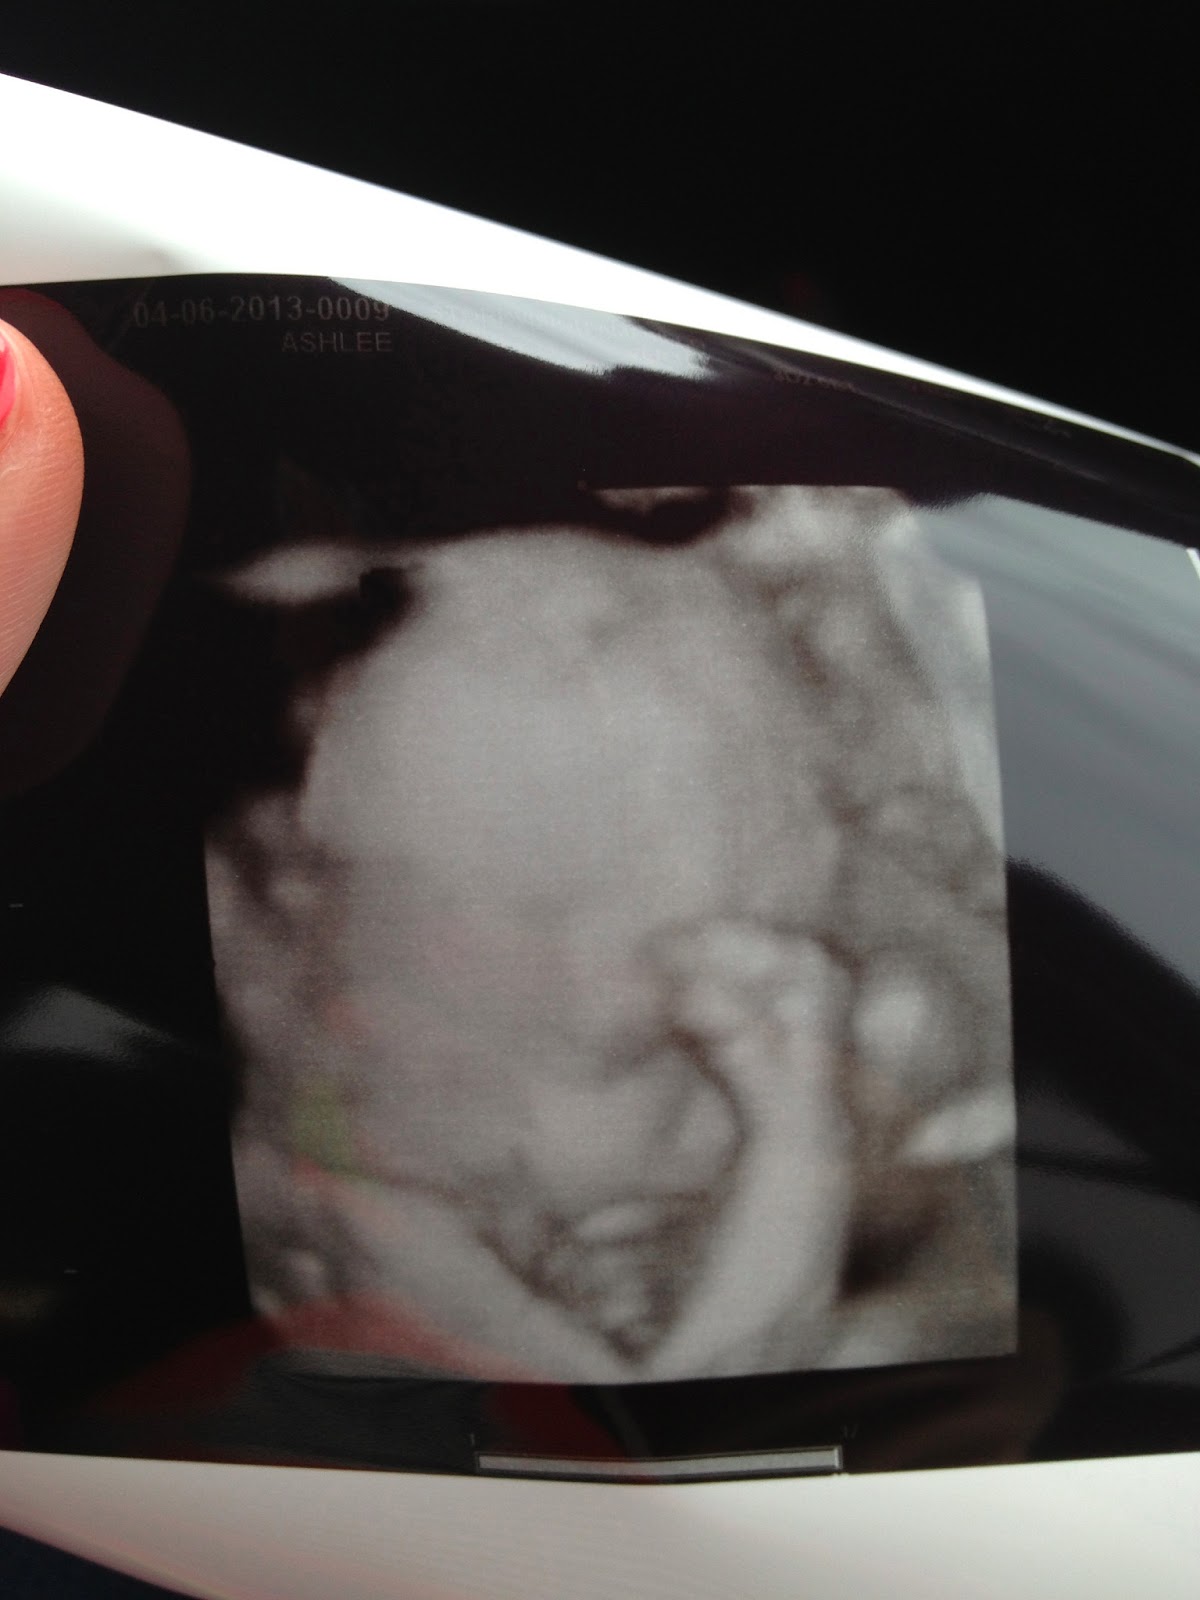

- Best Moment of the Week: Seeing Little Miss in a 3d/4d sonogram, getting her bedding in…and I LOVE IT….and having our first shower given by my “school family”. It’s been a busy, fun and exhausting week! 🙂

Here are some pictures from the sonogram!30 weeks!